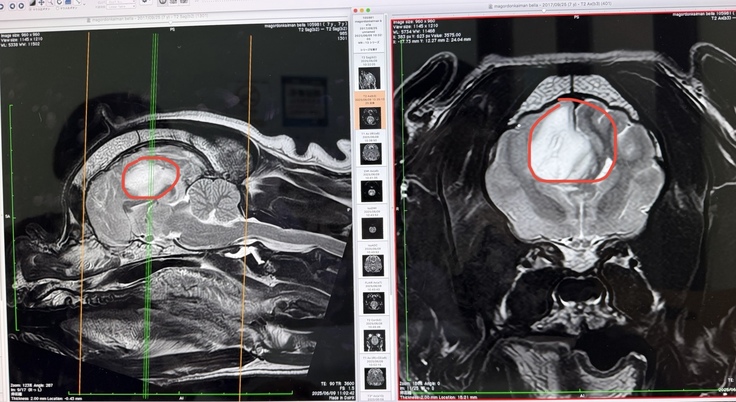

そこで、念のためMRI検査を勧められ、6月9日に検査を受けたところ、右脳に2cmの腫瘍(グリオーマ)が見つかったのです。

まさかそんな大きな腫瘍が見つかるとは思ってもおらず、家族全員が本当に信じられませんでした。つい数日前まで健康そのもの、どこも悪くなかったベラに、なぜこんな不運が降りかかってしまったのか…と、今でも胸が締め付けられる思いです。

それまで元気いっぱいで、家族みんなで代々木公園のドッグランに行ったり、家で引っ張りっこをしたり、明るくアクティブな女の子でしたが、発作以降は方向感覚がなくなり、家のベッドの場所もわからなくなり、散歩も短時間しかできなくなりました。他の犬と遊ぶことも発作のリスクがあるため控えざるを得ず、以前のような生活ができなくなっています。獣医師からは、この腫瘍が症状の原因と説明されています。